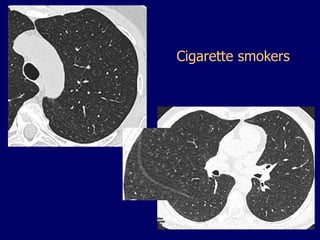

Cigarette smokers

2x cigarette smokers

(<65 years old)

80 year old

73 year old